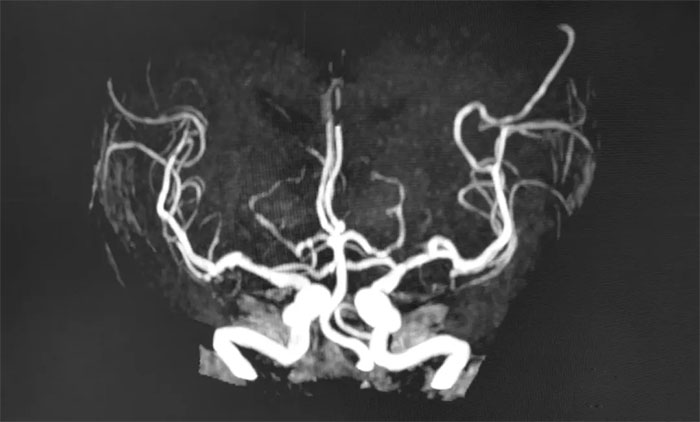

▲ MRA顯示顱底動(dòng)脈多發(fā)局灶性狹窄

MRA是基于飽和效應(yīng)、流入增強(qiáng)效應(yīng)、流動(dòng)去相位效應(yīng)顯示血管,可發(fā)現(xiàn)血管狹窄和閉塞的部位,以及血管病變(動(dòng)脈瘤、動(dòng)脈畸形等)。

MRA包括直接MRA與增強(qiáng)MRA(CE-MRA),二者各有優(yōu)勢。直接MRA不用對比劑,簡便無創(chuàng),成本低,對于顯示血管非常有其實(shí)用價(jià)值,已經(jīng)成為臨床不可少的檢查方法。CE-MRA對血管腔的顯示比直接MRA更為可靠,出現(xiàn)血管狹窄的假象明顯減少,血管狹窄程度的反映比較真實(shí)。對于腦血管病高危人群來講,定期做腦血管磁共振(MRA)檢查非常重要!